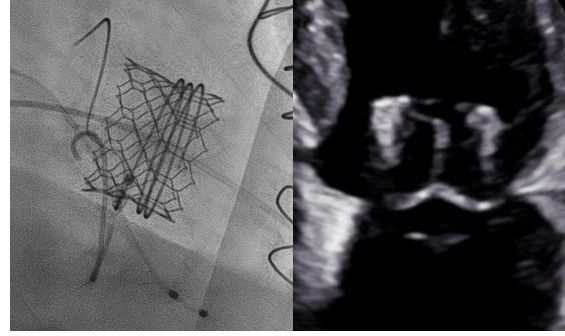

Bei Patient:innen mit hohem Operationsrisiko aufgrund schwerer Begleiterkrankungen, hohen Alters oder einer hochgradigen Einschränkung der Herzfunktion stellt die kathetergestützte Mitralklappenrekonstruktion mit MitraClip, dem Pascal- oder dem Carillon-System eine sehr gute Therapiealternative dar. Weiters können wir auch den perkutanen Mitralklappenersatz mittels Edwards M3 anbieten. Diese Eingriffe erfolgen meist unter Vollnarkose und werden mit Hilfe eines Kathetersystems über die Leistenvene durchgeführt und mittels Herzultraschall geleitet.